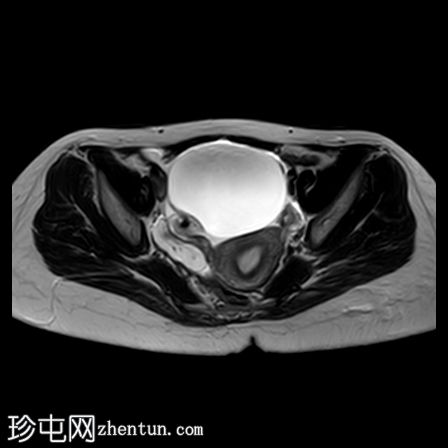

轴位

T1加权像

DWI

右侧卵巢增大,卵泡呈周边排列。

附件血管蒂扭转(漩涡征)。

右侧附件旁可见一较大的、边界清晰的盆腔囊性病变,向右倾斜,提示为卵巢旁囊肿。

本病例展示了卵巢扭转的典型影像学特征,包括卵巢增大、卵泡呈周边移位、卵巢向内侧偏移以及特征性的漩涡征。

在这种情况下,较大的卵巢旁囊肿被认为是发生卵巢扭转的高危因素。如果卵巢旁囊肿较大(>5厘米)或活动度较大,其重量/活动度增加会牵拉附件,导致卵巢和输卵管发生扭转。